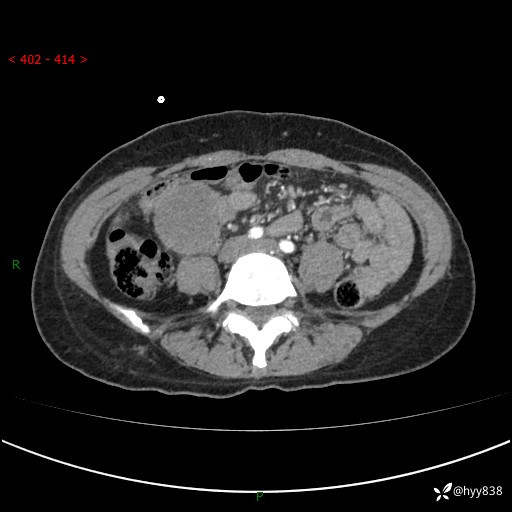

年轻女性,发现腹腔肿物1周。圆圆的肿物,诊断有难度---结果公布~

主诉:发现腹腔肿物1周

现病史:患者自诉于1周前无明显诱因出现剑突下间断性隐痛,尚可忍受,不向其它部位放射,无恶心呕吐、腹泻便秘等不适,于当地市第二人民医院就诊,行CT结果示:1.右中腹占位,间叶组织来源可能2.小肠梗阻3.盆腔积液4.腹腔积液5.副脾6.肝囊肿;于荆州二医行抗炎,抑酸,护胃,补液等对症支持治疗;患者病情好转,今为求进一步诊治,遂来我院门诊就诊,门诊以“腹腔肿瘤”收入院。 起病以来,患者精神、睡眠、饮食一般,大小便正常,近期体力体重无明显改变。

腹部CT增强(外院平扫)